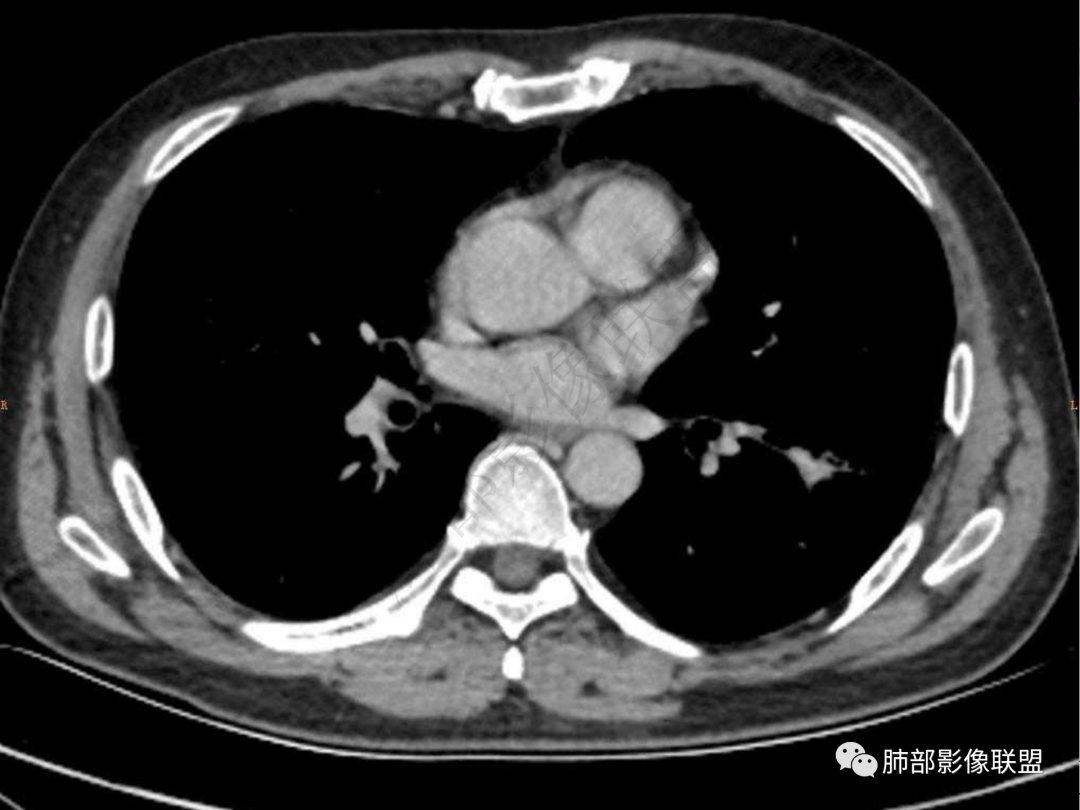

1.中年男性,咳嗽咳痰20余天,间断咯血2周

2.左肺下叶团片影,跨背段及内前基底段,实性部分类椭圆形,密度不甚均匀,可见毛刺及棘状突起,未见典型分叶及胸膜凹陷。病灶上下缘可见相应肺段支气管旁进侧出,管壁轻度增厚,未见狭窄阻塞。

4.实性部分不均匀环形强化并显示一小范围低密度坏死区或空洞。较之肺窗,整体纵隔窗范围较小,提示病灶并不十分密实。抑或为不同时段图像。

5.双肺门及纵隔未见增大淋巴结。未见胸腔积液。

肺脓肿:可宽基底与胸膜相连,附近胸膜增厚——炎性特点

肺脓肿:边界模糊不清,或者块影为类圆形,无明显分叶,边缘平直为主,刀切征——炎性特点三、病灶周围特点:肺脓肿:病灶非远端有片状GGO——炎性特点四、近端支气管阻塞:肺脓肿:常有引流支气管伴管壁增厚或者支气管沿洞壁走行。五:坏死壁:肺脓肿:大多壁厚,少数壁薄,没有壁结节,内壁清楚光整——炎性特点

肺脓肿:环形强化,强化较显著。如出现明显囊壁样强化甚至边缘“憩室”样突出,高度支持肺脓肿。